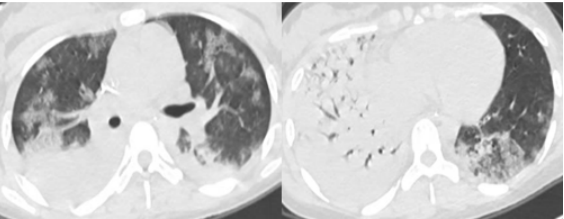

患者女性,15岁,学生。主诉:咳嗽咳痰10天,发热1周,呼吸困难4天。诊断为重症支原体肺炎,重度ARDS。

图片

予患者高流量氧疗、无创通气、气管插管有创通气、俯卧位,但其低氧血症和高碳酸血症均无法纠正,最终启动VV-ECMO,整体治疗效果较好。7天后撤机。但患者并发泛耐药鲍曼不动杆菌肺脓肿脓胸,胸水浑浊,胸水培养和BALF培养均为泛耐药鲍曼不动杆菌。

经过反复胸腔闭式引流,多黏菌素B+替加环素(21天)/多西环素+美罗培南(8天)抗感染,患者好转出院,出院后1个月和4个月复查肺部CT,可见病灶吸收良好。尽管如此,院内感染仍然延长了患者的住院时间,增加了医疗费用。因此,ECMO救治过程中一定要警惕并发症的发生。